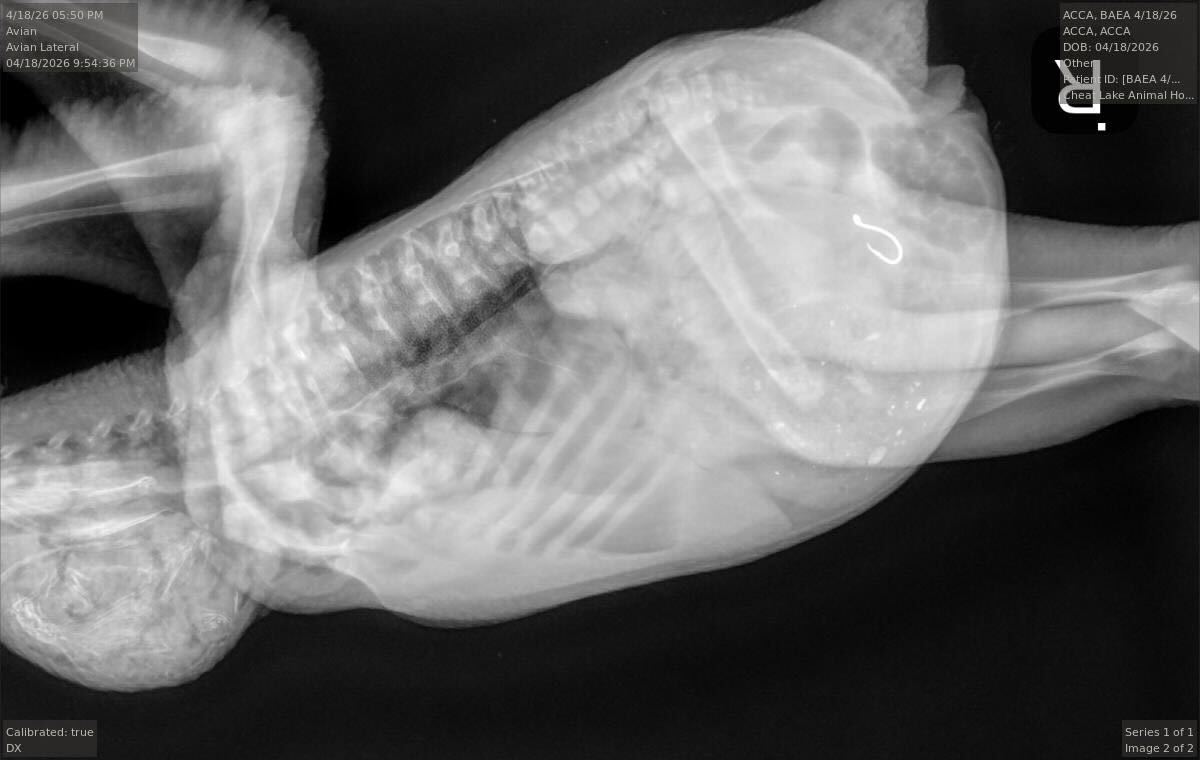

An X-ray of the eaglet, showing the fishhook in its stomach.

(Dr. Jesse Fallon/Avian Conservation Center of Appalachia / FOX Weather)

The eaglet's X-ray, showing the fishhook in its stomach.